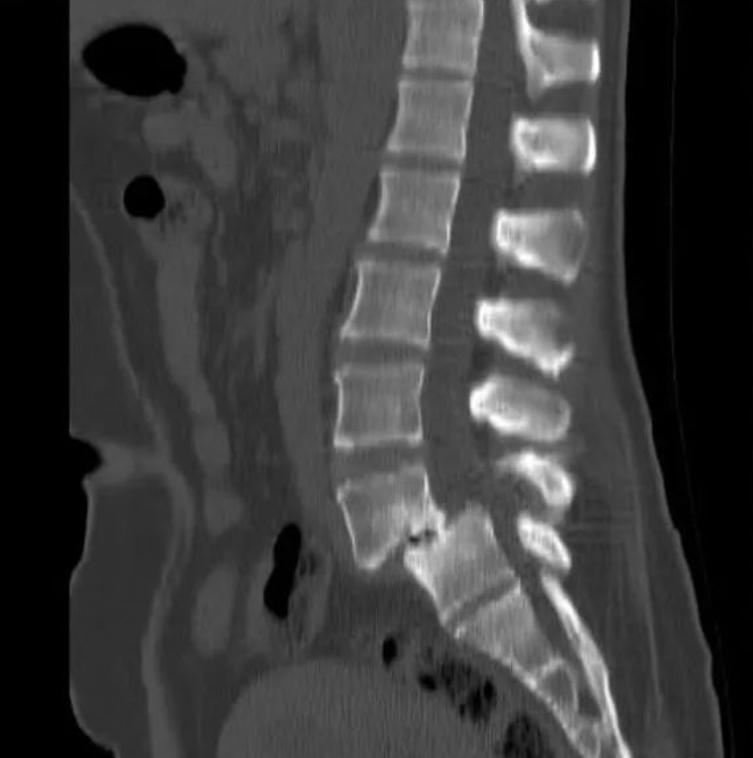

CT扫描

椎弓根下层面可见2~9cm锯齿样裂隙,宽窄不一,走行不定,扫描倾斜时与椎间盘层面正常光滑关节面呈双关节面。

椎管前后径延长,可呈“双管征”。

滑脱椎体“双边征”

椎间盘于相邻椎体层面以相反方向超出椎体边缘“夹心征”。

核磁共振检查(MRI)

核磁共振检查(MRI)可观察腰椎神经根受压情况及各椎间盘退变程度,有助于确定减压和融合范围。

椎弓峡部崩裂面粗糙的低信号带

双关节征、双边征和椎间盘夹心征